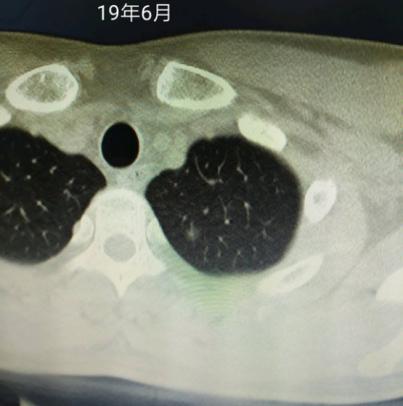

直到根据ct变化明显看到患者结节长大了2-3mm,我判断大概率微浸润了后,才断定可以手术了。手术完后不出所料,微浸润腺癌。

2019-06-30

亲爱的戴主任,我半年前咨询过您的,现在这情况咨询下您的意见,有没有必要到您医院来一下。半年前才5mm这次8mm,感谢!

最早只有一个0.6磨玻璃,去年疫情前复查0.8咨询过戴主任您,今年复查变成多发了,麻烦戴主任您帮我看看,这个今年复查的,我们这里还有个女病友去重庆找过您看过,您跟她说的原位,她回来切了果然是原位,佩服得很,托我在这里跟你道个谢,感谢您!

大概率微浸润了。楔形切除小手术还可以根治。

今日大病理出来了,微侵润。走过了5年还是没逃脱挨刀的命,19年肺炎住院查出结节,医生看了发现我17年的体检就有这个结节了,当时恐慌的不行连续好几天没有休息好,出院后到处咨询提心吊胆的,有幸在贴吧碰上戴主任在为病友看片解答,便将自己的片子报告贴在了吧里,没想到主任半夜还给我回复了,因为比较小对比17年的没变化,主任就说先随访,毕竟手术是不可逆的伤害,当时心里一下就踏实就,感觉就是一剂强效安心针,彻底地缓解了自己的焦虑状态。

后面就在吧里看主任的帖子学了很多知识,复查了2年没有变化,本以为会一直这样复查下去没有变化到老去。奈何天不遂意,人生多坎坷,21年底的复查发现由原来的0.6变大成0.8了,还在别的位置多发了结节,当时复查的医生看了对比20年的片子说没有多大变化建议随访。但是我看戴主任说的有变化就要谨慎对待,所以我又将片子报告传到贴吧请求主任再帮我看看,还是一样的,主任大晚上给我回复了,判断我的现在大概率原位小概率微,看到这里我知道我不能等了,因为疫情没办法去找主任亲手解决问题,就在华西挂了号,主刀医生看我的确实有变化也就给我排了手术。手术做的很成功,术中病理报的腺癌,这个有心理准备还好,因为主任给我预估了我的病理,今天去取了大病理微侵润,我以为我的会是原位的,唉。人生不如意之事太多太多了,这里还是要感恩戴主任,让我无比坚决的要去手术,不然又不知道拖到什么时候了,感谢,感谢!这个是大病理,麻烦戴主任再给我看看。